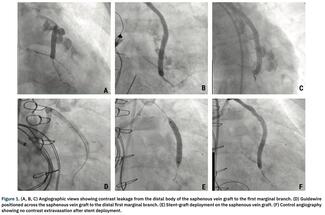

Denise Pellegrini, MD; Eduardo Saadi, MD, PhD; Ricardo Lasevitch, MD; Diego Pinheiro, MD; Ricardo Soccol, MD; Vitor O. Gomes, MD, PhD; Paulo Caramori, MD, PhD; Gustavo L. Agostini, MD

A 58-year-old woman presented to the emergency department with a non-ST segment elevation myocardial infarction. She was referred for coronary artery bypass graft surgery due to severe multivessel coronary artery disease. In the immediate...